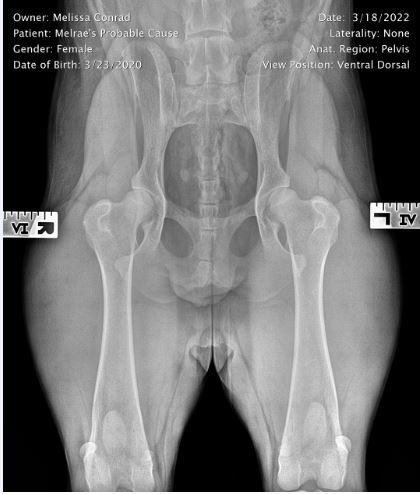

Melrae's Probable Cause

Hips: Excellent